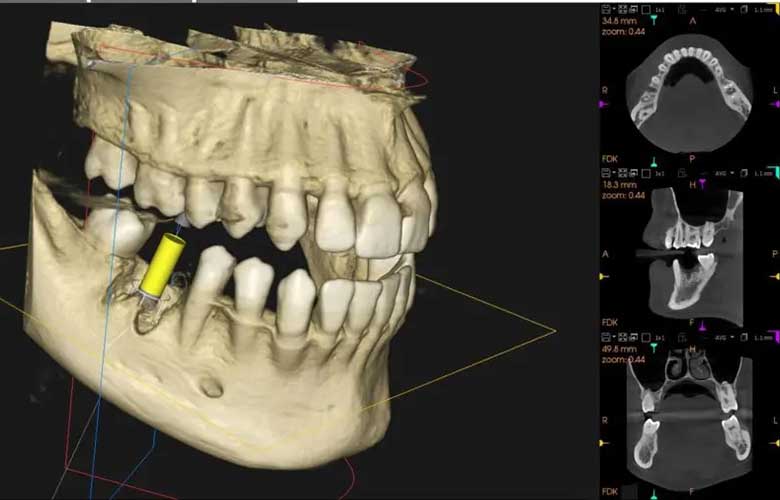

歯科用CTによる「3次元診断」

インプラント治療や親知らずの抜歯、難しい根管治療を検討されている方には、歯科用CTの画像をお見せします。

これまでの平面的なレントゲンでは分からなかった、顎の骨の厚み、神経との距離、骨の中の空洞などを3Dで可視化します。

「手術が必要な理由」や「安全性がどのように確保されているか」を、立体的な画像を見ながら詳しく解説します。